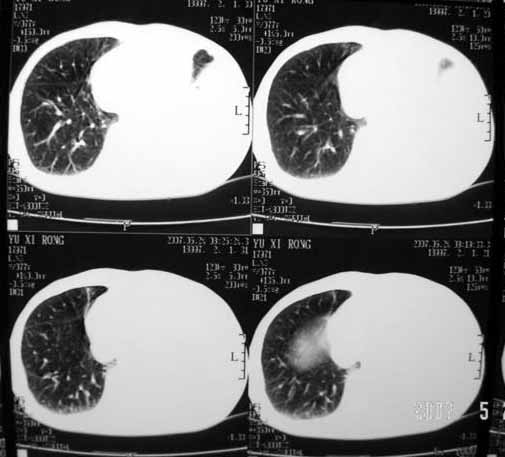

以下是引用luochengyi在2007-5-24 14:33:00的发言:[br]考虑左下肺癌。左侧胸腔积液。

以下是引用adams在2007-5-24 17:12:00的发言:[br]支持“考虑左下肺癌,左侧胸腔积液,建议胸水检查”。[br] [br]

以下是引用fumaogui在2007-5-24 16:20:00的发言:[br]左侧胸腔积液.[br]左下叶不张考虑中心型肺癌[br]建议纤支镜检查.